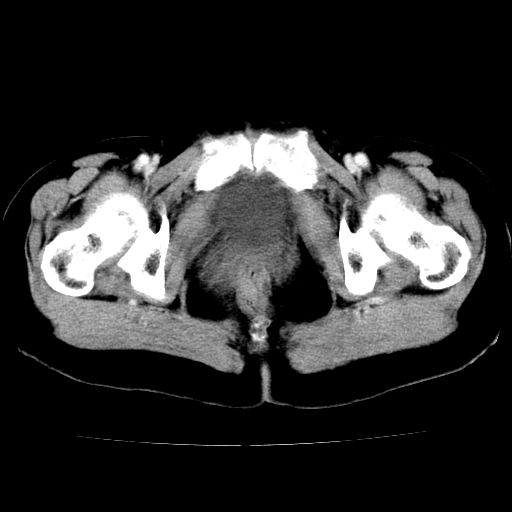

标题: CT24785:女,62岁,发现下腹部肿物半年。 [打印本页]

标题: CT24785:女,62岁,发现下腹部肿物半年。

女,62岁,发现下腹部肿物半年,下腹部不适。

老年女性患者,盆腔囊实性占位,ct增强不均匀强化,未见壁结节,未见腹水及盆腔积液,考虑附件囊腺瘤可能性大!

实性成分太多,要是囊腺瘤也要考虑恶性。